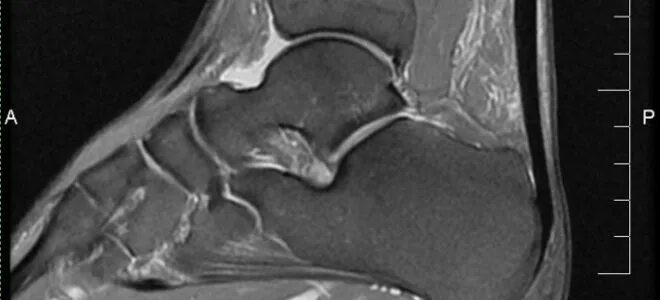

Мрт ахиллового сухожилия